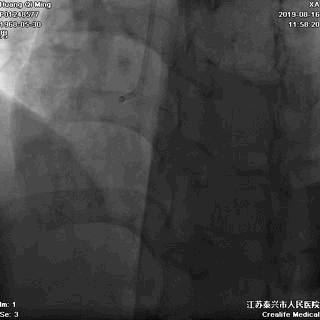

冠状动脉造影

右冠状动脉无严重狭窄

左主干前分叉处血管正常

LCX近中段病变,狭窄最重达90%

LAD中远段血管偏细,弥漫性病变,狭窄达90%

介入治疗策略

LCX,PTCA+DES;

LAD,PTCA+切割球囊+NC球囊+药物洗脱球囊